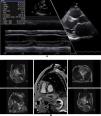

Clinical vignettesHypertrophic cardiomyopathy was first diagnosed in the female proband, individual II-1 (Figure 1B) at the age of 45 years when she developed paroxysmal atrial fibrillation (AF) after non-cardiac surgery. At that time, she was classified in New York Heart Association (NYHA) class II. Her physical examination revealed a systolic murmur at the left sternal border and aortic area that increased during orthostatism. The ECG showed sinus rhythm, left atrial dilatation, left axis deviation, pathological Q waves in aVF and DIII, V1 to V4, and SV2+RV6=35 mm, without ST-T changes. Transthoracic echocardiography showed asymmetrical hypertrophy of the anterior and inferior septum (neutral septal morphology) and lateral wall (maximal wall thickness 20 mm), without apical involvement (Figure 3). The left ventricle was non-dilated and left ventricular (LV) ejection fraction was preserved. The left atrium (LA) was dilated and there was evidence of elevated LV filling pressures (E/e′15+LA dilatation+tricuspid regurgitation velocity>2.8 m/s). The resting peak left ventricular outflow tract (LVOT) gradient was 61 mm Hg and mild to moderate systolic anterior motion (SAM) dependent mitral regurgitation was present. Systolic pulmonary artery pressure was estimated at 43 mmHg (38+5). Tissue Doppler imaging showed low s’ and e’ velocities at the mitral annulus. CMR was not performed. She began to take bisoprolol and oral anticoagulation (subsequently discontinued because of concomitant alcoholic liver disease) and remained clinically stable for 14 years. She died in 2003 at the age of 59, from a liver disease complication; she had no offspring.

Echocardiogram from the index patient II-1 (performed at the age of 54). Parasternal long axis view, two-dimensional and M-mode, showing asymmetric septal hypertrophy and mitral valve systolic anterior motion. Apical four chamber view and color wave Doppler show major left ventricular outflow tract obstruction. Please note that these 18-years-old echocardiographic images are suboptimal quality since they were obtained from still frames from thermal paper. Unfortunately, there are no better quality images available.

The affected brother (individual II-2), now aged 86, has an HCM phenotype, detected when he was 67 after genetic cascade screening. Although asymptomatic at diagnosis, he developed AF and has slow-progressing congestive right heart failure, now in NYHA III, with multiple hospitalizations in the past year. He reports no chest pain or syncope. His first ECG (Figure 4A) showed sinus rhythm, no LV hypertrophy criteria and marked ST-T changes in the precordial leads. His echocardiogram showed asymmetric hypertrophy, neutral septal morphology (21 mm maximal wall thickness) and no obstruction, neither at rest nor with bedside provocation maneuvers (Figure 5A). LV ejection fraction was preserved. When in sinus rhythm the E/e’ was 17. The right chambers were dilated and the right ventricle had reduced longitudinal function. He also had moderate pulmonary hypertension, 55 mmHg (45+10). His CMR revealed intramural late gadolinium enhancement in the hypertrophic segments, as well as in the insertion zone of the right ventricle in the lower interventricular septum (Figure 5B). Later, he developed AF, and right axis deviation (Figure 4B). There is no evidence of significant ventricular arrhythmias other than a single asymptomatic ventricular triplet in the 24-h ECG monitoring (Figure 4C). His European Society of Cardiology (ESC) HCM Risk-SCD is low (five-year risk <4%).3 Concomitant pulmonary embolism was excluded. He is currently taking rivaroxaban, bisoprolol, furosemide and spironolactone.

Echocardiogram and cardiac magnetic resonance imaging from patient II-2 (performed at the age of 84 years). A: Transthoracic echocardiogram, parasternal long axis view, 2-dimensional and M-mode, also showing asymmetric septal hypertrophy. B: These cardiac magnetic resonance images confirm the echocardiographic findings (asymmetric septal hypertrophy and mild mitral regurgitation) and provide tissue characterization data, with late gadolinium enhancement in the interventricular septum and in right ventricular insertion point in interventricular septum, typical findings of HCM.